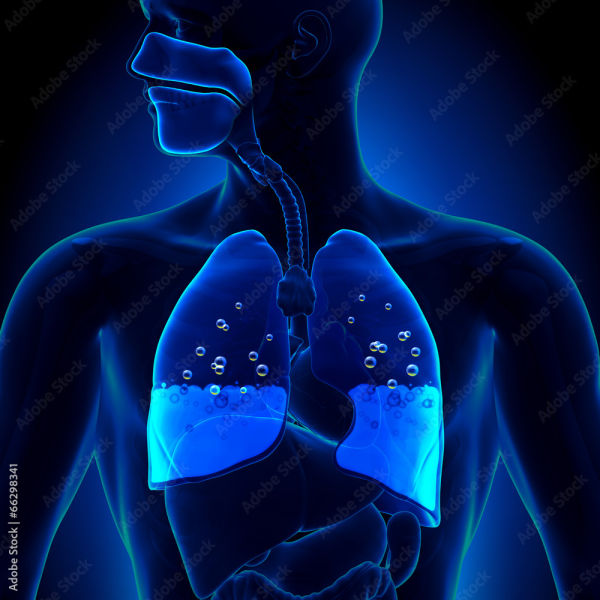

Filling of water in the lungs, known as pulmonary edema, is a serious health problem. This condition occurs when fluid starts accumulating abnormally in the lungs. Experts say that if not identified and treated on time, it can become life threatening.

Due to filling of lungs with water

Main symptoms of water filling in lungs

According to experts, it is very important to recognize this condition in time. Its common symptoms are:

Sudden difficulty breathing or shortness of breath.

Cough, which may sometimes produce foamy discharge.

Heaviness or pain in the chest.

Extreme fatigue and weakness.

Blue or pale lips and fingers, which are a sign of lack of oxygen.

Swelling in the feet and ankles, which shows an imbalance of fluids in the body.